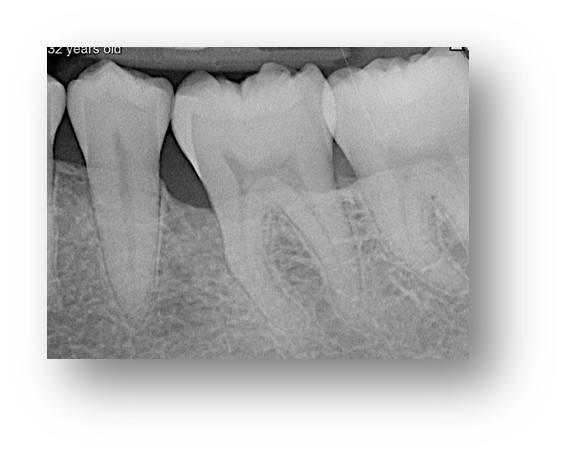

![]() | ![]() |

| Before and after surgery to reshape gums | X-ray showing results before and after bone graft surgery |